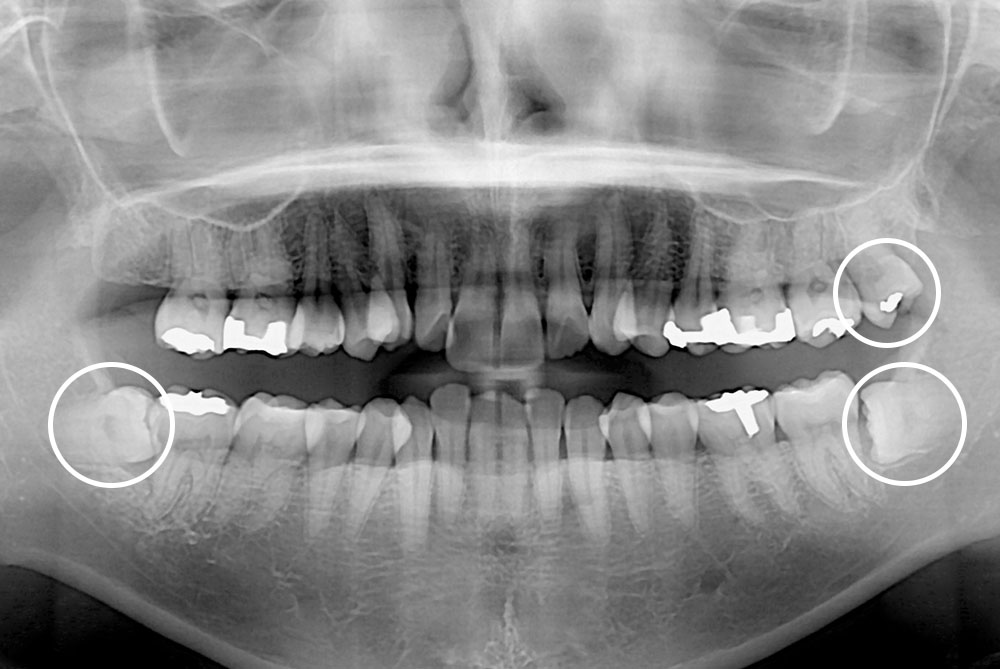

[사랑니] 매복 사랑니 발치

치료전 : 2018-09-20